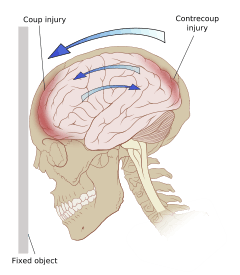

Even in the absence of an impact, significant acceleration or deceleration of the head can cause TBI; however in most cases a combination of impact and acceleration is probably to blame.[30] Forces involving the head striking or being struck by something, termed contact or impact loading, are the cause of most focal injuries, and movement of the brain within the skull, termed noncontact or inertial loading, usually causes diffuse injuries.[12] The violent shaking of an infant that causes shaken baby syndrome commonly manifests as diffuse injury.[60] In impact loading, the force sends shock waves through the skull and brain, resulting in tissue damage.[30] Shock waves caused by penetrating injuries can also destroy tissue along the path of a projectile, compounding the damage caused by the missile itself.[15]

Damage may occur directly under the site of impact, or it may occur on the side opposite the impact (coup and contrecoup injury, respectively).[59] When a moving object impacts the stationary head, coup injuries are typical,[61] while contrecoup injuries are usually produced when the moving head strikes a stationary object.[62]